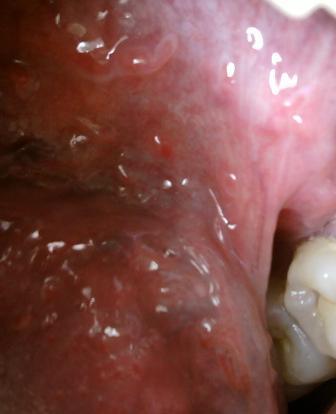

尖锐湿疣潜伏期多长时间一般是通过以下三种途径来感染尖锐湿疣病毒的:直接接触传染,间接接触传染和母婴传染,感染病毒之后并不会立即发病,而是有一定时间的潜伏期,一般是三个月左右的时间,但是不同的人身体素质的差异,因此具体时间是不同的,潜伏期并没有什么明显的症状表现,不容易被人们察觉。初期病情轻微希望此时,患者应该及时就诊,经过科学的诊治,坚持治疗,疾病是可以治愈的。